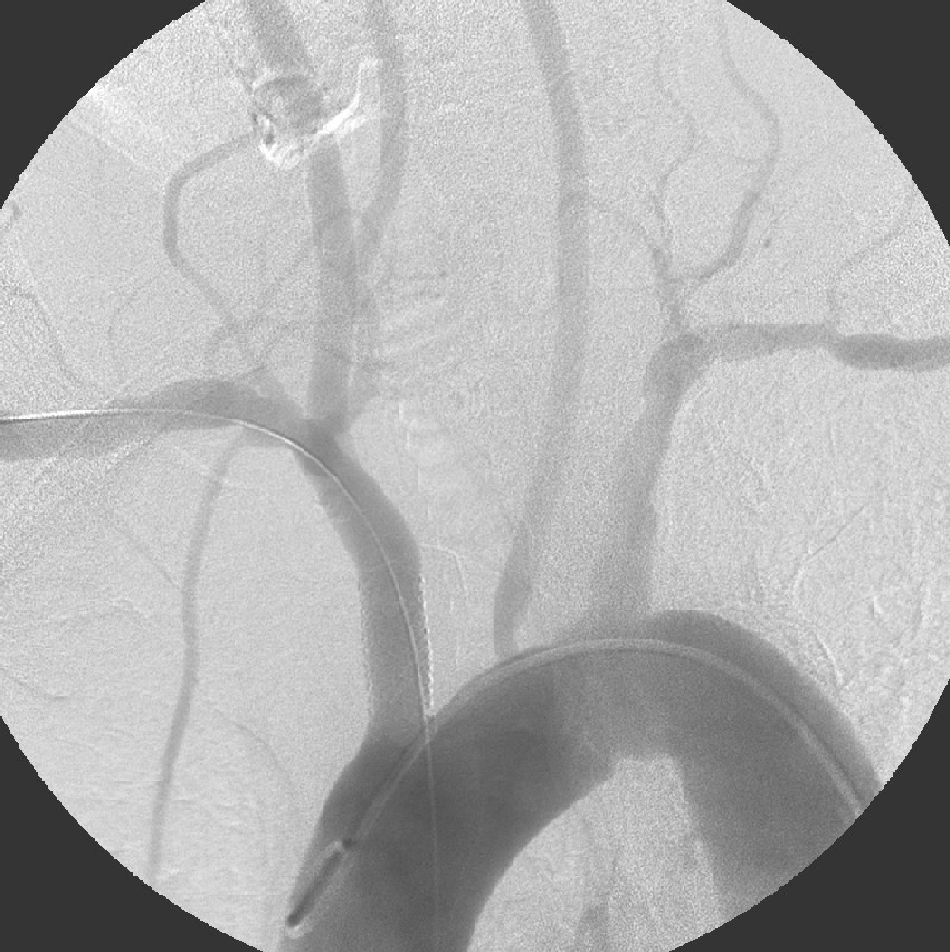

Figure 2 Innominate artery stenting in a 56-year-old man.

(A): Angiography showed a soft and irregular plaque conditioning a subocclusive stenosis of the innominate artery.

(B): Control angiography following direct stent graft implantation.